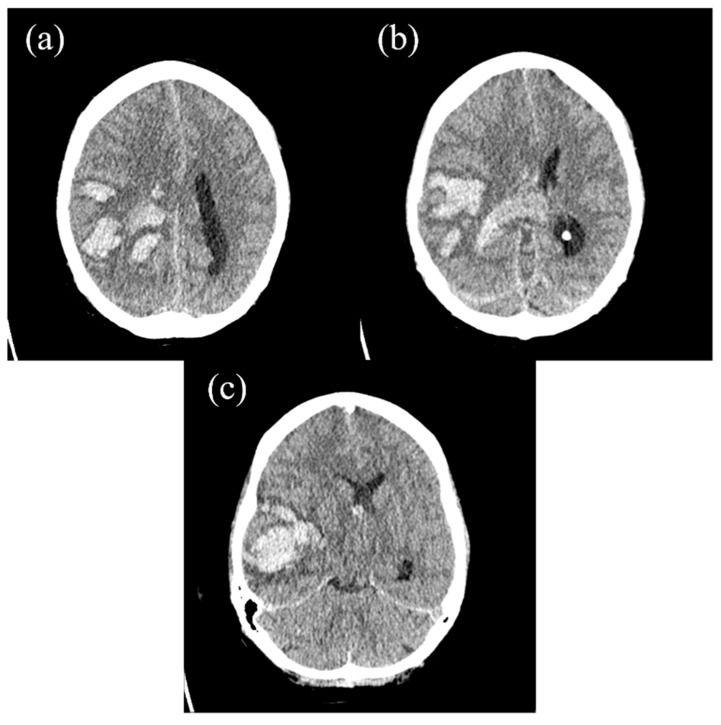

背景和临床意义:急性白血病是由未成熟前体细胞(“母细胞”)广泛增殖引起的造血系统肿瘤,主要发生在骨髓中。它们通常表现为模糊和非特异性的临床症状,使早期诊断特别具有挑战性。病例介绍:本病例报告描述了一位女性患者的临床过程,她最初因持续的牙痛而寻求牙科护理,这是一种非典型和误导性的症状。随后的检查显示诊断为急性白血病。虽然恶性肿瘤被及时发现并采取了适当的治疗措施,但疾病的发展速度惊人。患者最终出现了大量脑出血,这是一种可能与白血病相关凝血功能障碍有关的毁灭性并发症。尽管紧急的神经外科手术介入,出血证明是致命的。结论:该病例强调了在出现异常症状时提高临床怀疑的必要性,并说明了血液恶性肿瘤和凝血并发症之间复杂的相互作用。

Background and Clinical significance: Acute leukemias are neoplasms of the hematopoietic system that are caused by the extensive proliferation of immature precursor cells ('blasts'), mainly in the bone marrow. They frequently manifest with vague and non-specific clinical symptoms, making early diagnosis particularly challenging. Case Presentation: This case report describes the clinical course of a female patient who initially sought dental care due to a persistent toothache-an atypical and misleading symptom. Subsequent investigations revealed a diagnosis of acute leukemia. Although the malignancy was identified promptly and the appropriate therapeutic measures were initiated, the disease progressed with alarming rapidity. The patient ultimately developed a massive intracerebral hemorrhage-a devastating complication likely related to leukemia-associated coagulopathy. Despite emergent neurosurgical intervention, the hemorrhage proved fatal. Conclusions: This case highlights the critical need for heightened clinical suspicion in the presence of unusual symptoms and illustrates the complex interplay between hematologic malignancies and coagulopathic complications.